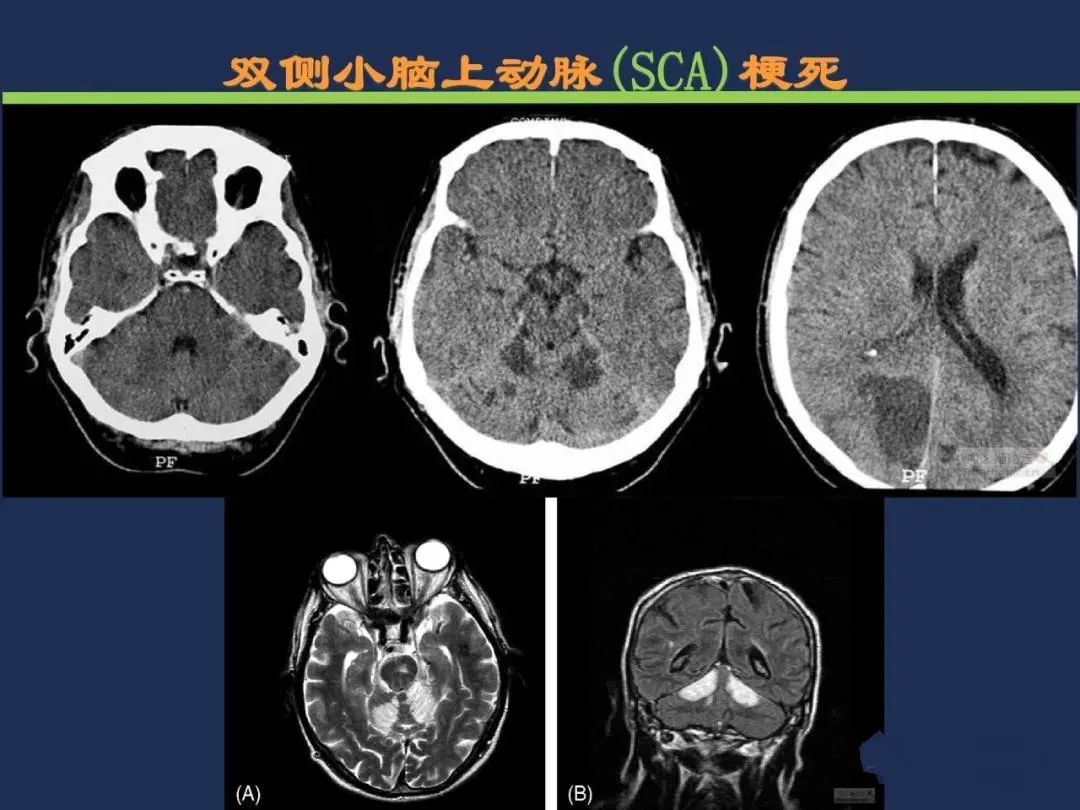

小脑前上动脉